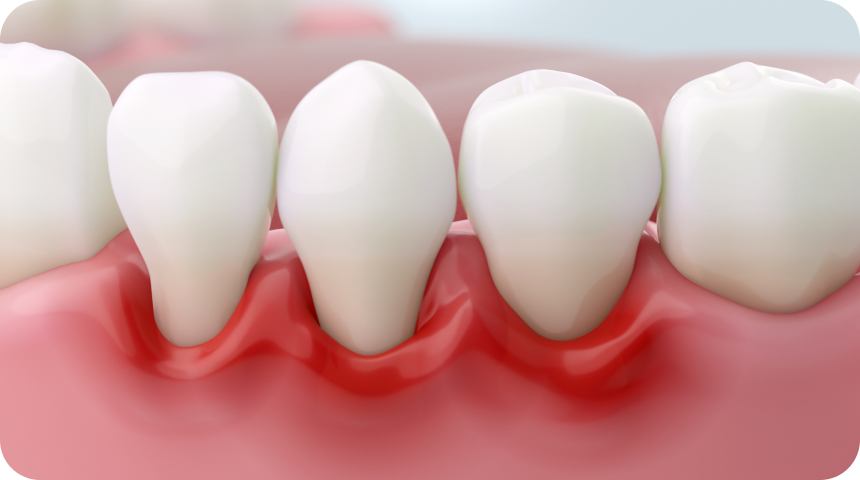

Vos gencives saignent ou sont douloureuses ? Elles se rétractent ? Il s’agit peut-être des premiers signes d’une maladie parodontale. Pour mettre fin aux douleurs et pour retrouver un beau sourire, une prise en charge médicale de la pathologie est nécessaire. Le Dr Benichou, chirurgien-dentiste et spécialiste dans la parodontologie à Toulouse, peut traiter toutes les maladies parodontales même les cas les plus avancés.

La maladie parodontale, aussi appelée parodontite, est une affection de la cavité buccale. C’est une pathologie inflammatoire d’origine bactérienne dont le facteur déclenchant principal est la plaque dentaire. L’inflammation provoquée par des bactéries va détruire petit à petit tout le système d’attache des dents jusqu’à les rendre mobiles.

Les symptômes classiques d’une atteinte inflammatoire des gencives sont le saignement pendant le brossage des dents, ou encore plus grave, le saignement spontané des dents et des gencives. Les autres signes qui peuvent apparaître sont les mobilités et les migrations dentaires, ainsi que la mauvaise haleine. Dans cette situation, il est important de mettre en place des soins dentaires adaptés pour retrouver une bonne santé gingivale.

- la gingivite : inflammation de la gencive ;

- la parodontite débutante : évolution d’une gingivite non soignée ;

- la parodontite modérée : stade dans lequel les gencives se rétractent en créant un espace entre la dent et la gencive ;

- la parodontite avancée : apparition de poches parodontales profondes avec perte osseuse. On observe alors un déchaussement des dents, et dans les cas les plus graves, la perte des dents.